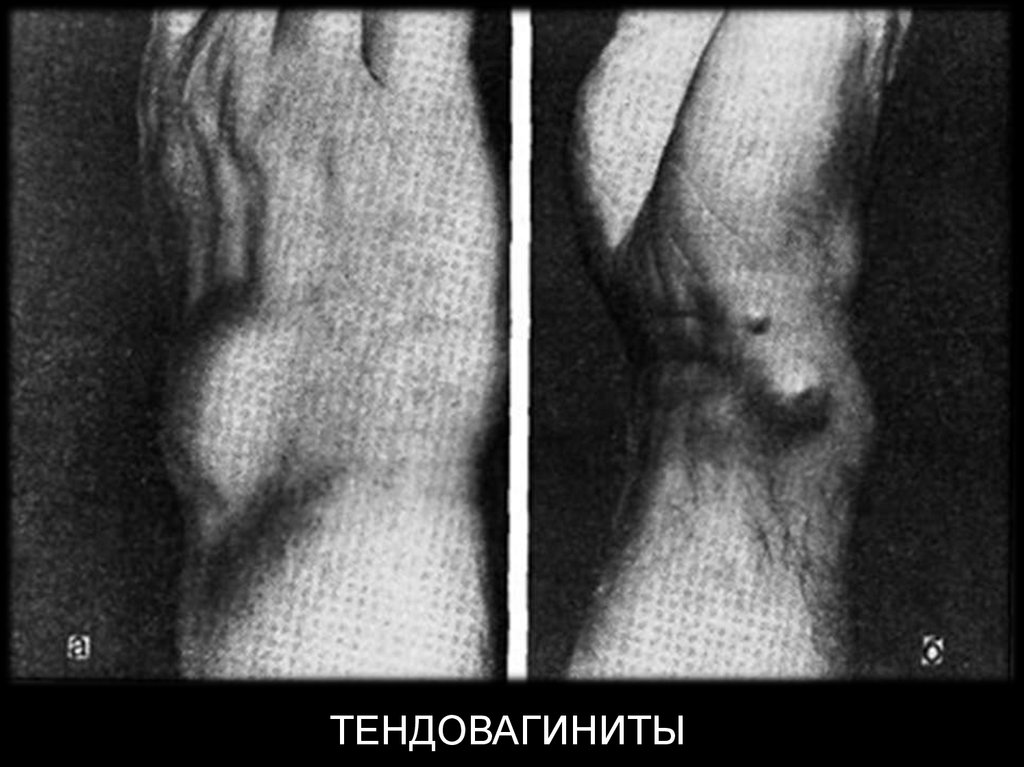

ТЕНДОВАГИНИТЫ